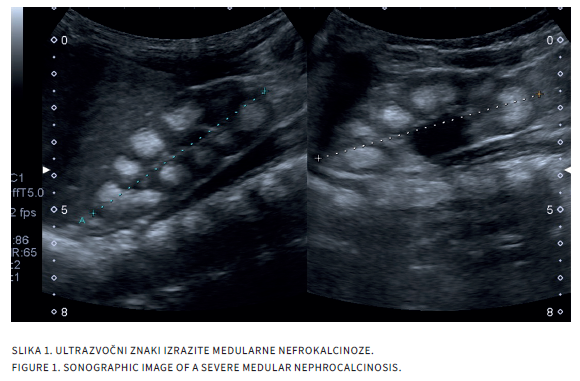

FAMILIARNA HIPOMAGNEZEMIJA S HIPERKALCIURIJO IN NEFROKALCINOZO

Družinska hipomagnezemija s hiperkalciurijo in nefrokalcinozo (angl. familial hypomagnesemia with hypercalciuria and nephrocalcinosis, FHHNC) je redka avtosomno recesivna presnovna bolezen s prizadetostjo ledvičnih tubulov. Zanjo je značilna izgubljanje magnezija in kalcija preko ledvic s pridruženo nefrokalcinozo in/ali ledvičnimi kamni že v zgodnjem otroštvu, zaradi česar gre tudi za napredujočo ledvično okvaro, ki se klinično izrazi v drugem ali tretjem desetletju življenja. FHHNC uvrščamo med redke presnovne vzroke za nastanek ledvičnih kamnov, nefrokalcinoze in kronične ledvične bolezni pri otrocih. Zaradi neizogibne napredujoče in nepovratne okvare ledvic pa moramo pri vseh otrocih, pri katerih odkrijemo ledvične kamne ali nefrokalcinozo, pomisliti tudi na redke presnovne razloge za njihov nastanek, saj lahko samo z doslednimi simptomatskimi ukrepi podaljšamo čas do nastanka kronične ledvične okvare in s tem pomembno izboljšamo kakovost življenja.